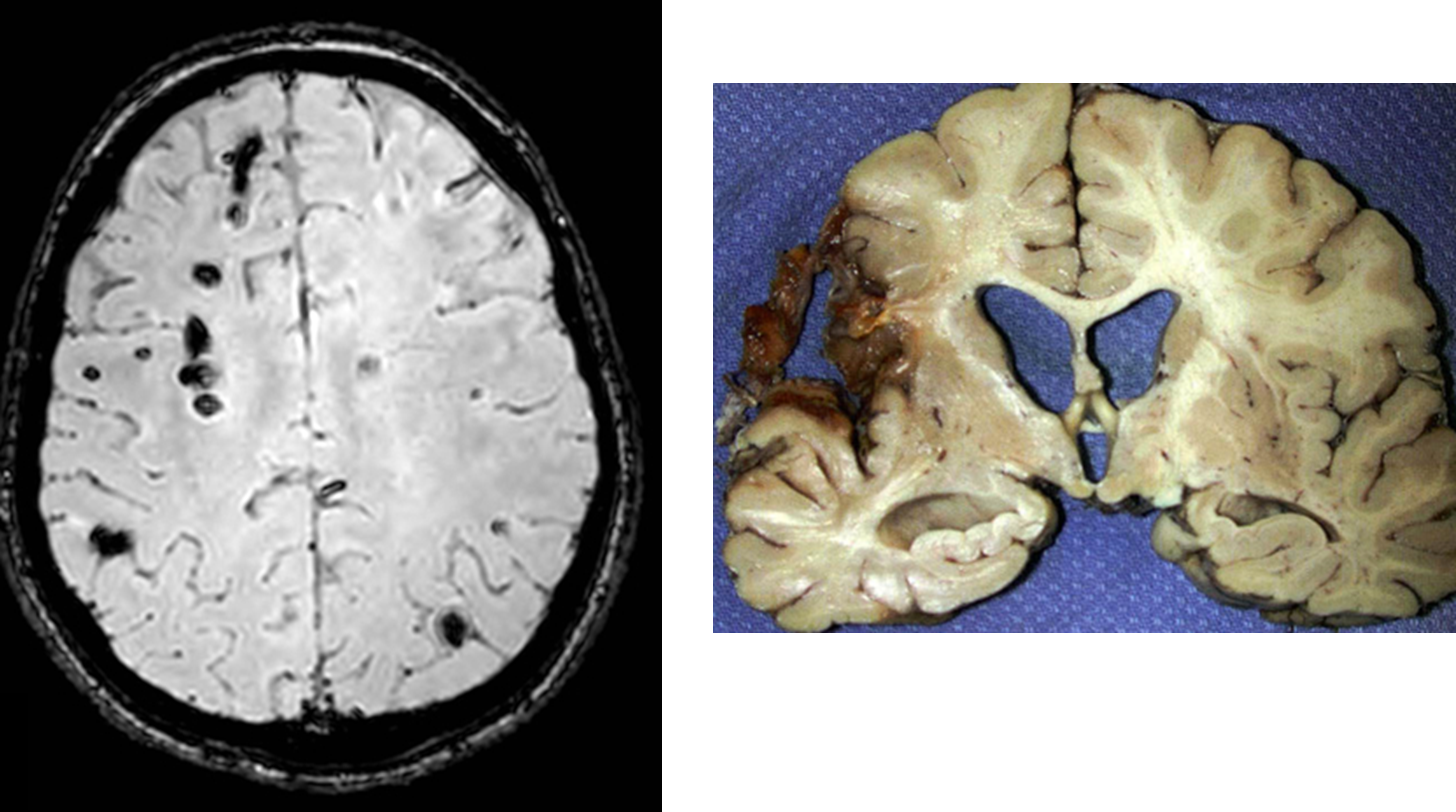

What is Amyloid Angiopathy?

Cerebral Amyloid Angiopathy is when amyloid beta peptide deposits within small to medium sized blood vessels, often causing an intraparenchymal hemorrhage

1) May present with progressive cognitive decline and stroke like episodes

→ the peptides will weaken blood vessels causing microbleeds, which are often asymptomatic but can lead to bigger bleeds

2) These typically present superficially and are referred to as lobar hemorrhages

→ hemorrhages that are hypertensive in origin are often deeper